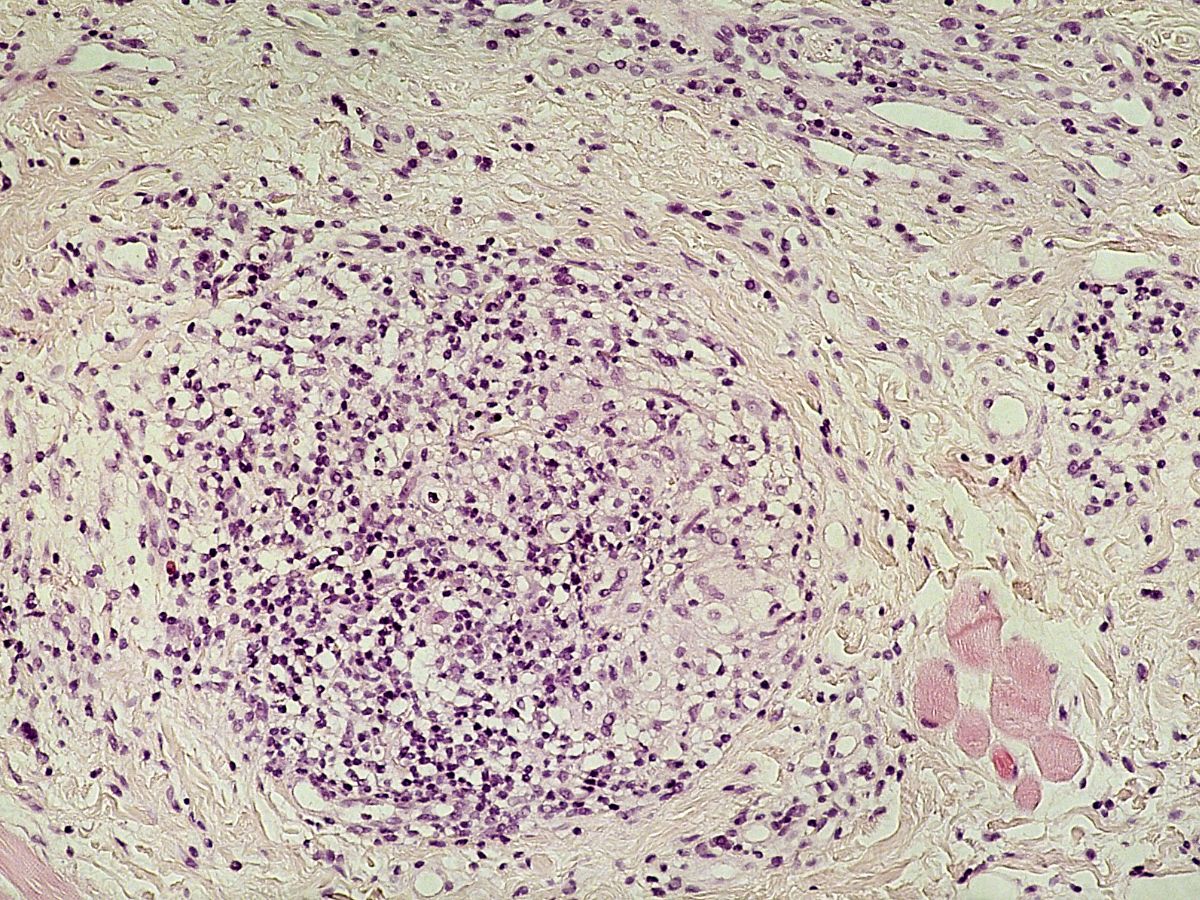

PA:- vroege stadia: oedeem en perivasculair infiltraat.

- later stadium: granuloomvorming, niet te onderscheiden van granuloomvorming

bij sarcoidosis of M.Crohn, soms soortgelijke afwijkingen in regionale lymfklieren.

![Cheilitis granulomatosa (click on photo to enlarge) [source: www.huidziekten.nl] Cheilitis granulomatosa](../../../images/cheilitis-granulomatosa-4z.jpg) |

![Cheilitis granulomatosa (click on photo to enlarge) [source: www.huidziekten.nl] Cheilitis granulomatosa](../../../images/cheilitis-granulomatosa-5z.jpg) |

![Cheilitis granulomatosa (click on photo to enlarge) [source: www.huidziekten.nl] Cheilitis granulomatosa](../../../images/cheilitis-granulomatosa-6z.jpg) |

| cheilitis

granulomatosa |

cheilitis